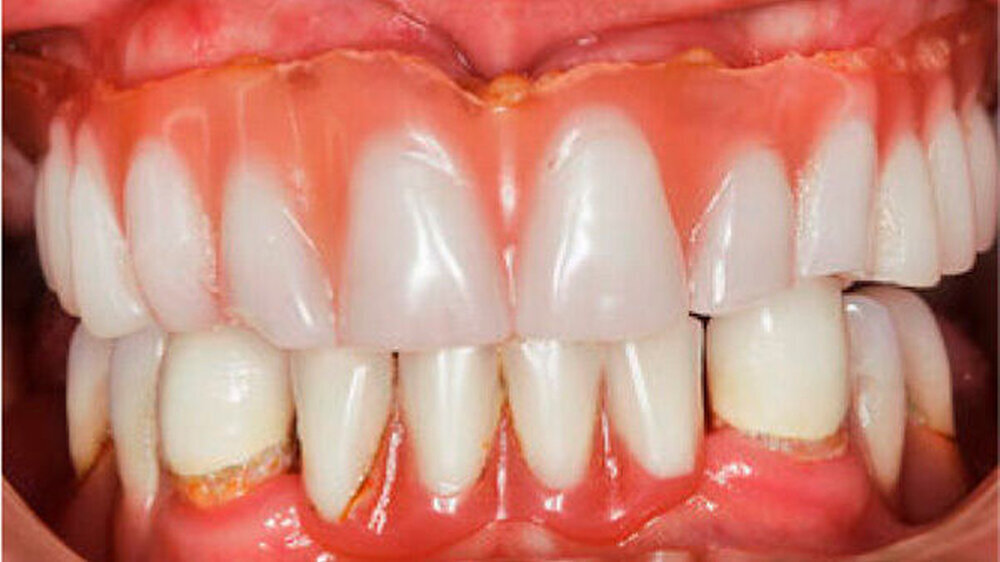

Der bei Behandlungsbeginn 14-jährige Patient war mit einer neun beziehungsweise fünfjährigen Prothese im Unter- beziehungsweise Oberkiefer versorgt (Abb. 2 und 3). Die angelegten Zapfenzähne 12, 11 und 21 waren bereits mehrfach konservierend restauriert und wiesen diverse Stellen mit Sekundärkaries auf. Die Kronenränder der Zähne 33 und 43 waren deutlich sondierbar. Der Kieferkamm im Unterkiefer war aufgrund der fehlenden Zahnanlagen sehr schmal (Abb. 4 bis 6). Die Panoramaschichtaufnahme zeigte das reduzierte vertikale Knochenangebot (Abb. 7). Da die Vitalerhaltung der wenigen Restzähne aufgrund des jungen Alters des Patienten unbedingt anzustreben war, wurde als Behandlungsziel im Ober- und Unterkiefer eine Versorgung mit Hybridprothesen, retiniert auf Teleskopkronen, festgelegt.

Durch Einbeziehung der Restbezahnung als Pfeilerzähne, und unter Beachtung deren Vitalerhaltung konnte der Patient funktionell und ästhetisch mit stabil verankerten Hybridprothesen rehabilitiert werden (Abb. 14 und 15). Teleskopkronen und -prothesen weisen Studien zufolge eine gute Langzeitprognose auf. Eine regelmäßige Nachsorge ist aber entscheidend für den Erfolg der Rekonstruktion. Da die Speichelmenge bei diesem Patienten im Normbereich liegt, ist diesbezüglich nicht von einem erhöhten Kariesrisiko auszugehen. Eine ungenügende Mundhygiene oder Mitarbeit hingegen stellen Risikofaktoren für biologische Komplikationen wie Parodontitis oder Karies dar. Nachteilig für den Erfolg der Rekonstruktion kann sich die relativ geringe Pfeilerzahl und deren Verteilung im Kiefer auswirken (Wöstmann et al. 2007).